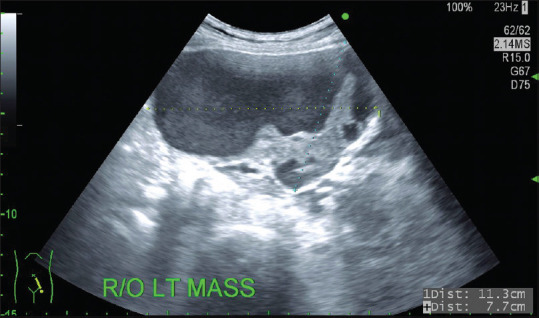

Endometriosis, adenomyosis, and uterine adenomyomas prevail most frequently in reproductive-age women. However, about 2%-4% of postmenopausal women may suffer from endometriosis symptoms, while adenomyosis does not occur frequently after menopause in the absence of exogenous hormones. While cystic adenomyosis is an uncommon variant of adenomyosis, it is even rarer to be pedunculated. Usually, degeneration is a feature of uterine leiomyoma, 4% of which might be cystic, while ruptured adenomyoma with cystic degeneration is only reported few times in the literature. We present a case of a 50-year-old menopausal woman, with a ruptured pedunculated adenomyoma with endometriotic cystic degeneration, with a literature review.